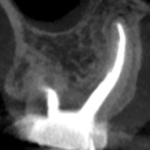

Pre-op

Post-op

臨床にも見事役立つ形成方法のコツであった。